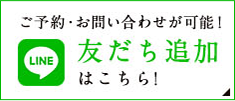

症例紹介29:インプラント治療/前歯_ソケットシール《50代女性》

年齢:50代

性別:女性

治療内容:食事中に前歯が破折し、治療を希望し来院。

術前の診査診断

術前写真

上顎:折れた歯を見ると、一部被せ物に歯が残っており保存不可能な状態。

レントゲン写真

上顎:歯には太い土台が入っており、折れて保存不可能な状態